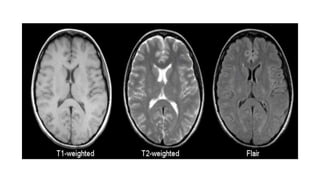

T1

• Provides the most anatomically-relevant images

• Fluid (in CSF and orbits) is dark

• Grey matter is darker than the white matter

T2

• Standard sequence

• Fluid is bright (hyper-intense)

• White matter is darker than grey

FLAIR (fluid attenuation inversion

recovery)

• Commonly used sequence

• Similar to T2, but the fluid is darker or "suppressed"

• Useful for areas of edema or inflammation